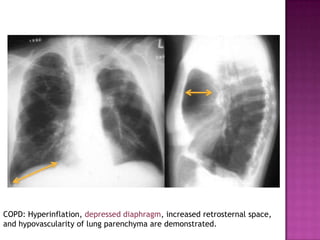

   Chest Radiography +/- CT scan

COPD: Hyperinflation, depressed diaphragm, increased retrosternal space,

and hypovascularity of lung parenchyma are demonstrated.